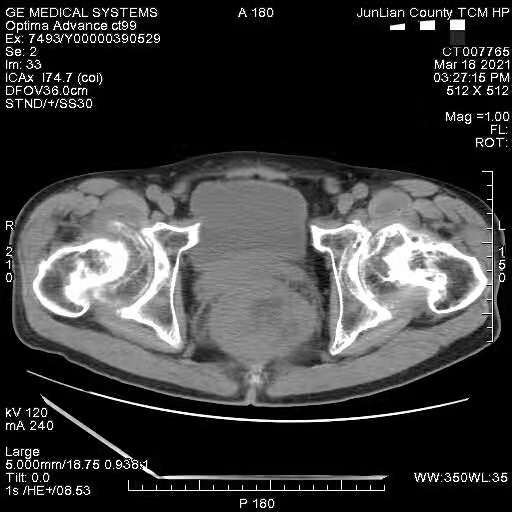

这个病人,在线的老师能帮我分析分析吗?这个病人4年前查出直肠肿瘤,未做特殊处理;间质瘤?现在我有两点疑惑:

1.回盲部区我看着觉得不对,肠壁增厚,阑尾增粗,好像软组织影也增多?

直肠及回盲部考虑肿瘤,双髋关节骨性关节病并股骨头坏死。

1、回盲区粪便影沉积,不考虑肿瘤。阑尾增粗?没看见,请箭头标注,大家一起来看看。

2、直肠区肿瘤,腔外生长型,因为没有肠梗阻;不除外盆腔的间质瘤。

直肠考虑肿瘤病变